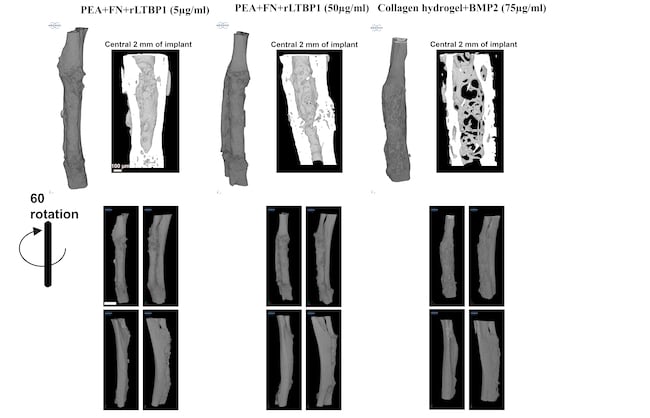

W ten sposób powstał niezwykły implant złożony z PEA, fibronektyny i rLTBP1. Wprowadzono go do ubytku kości u myszy i poprzez mechaniczne pociągnięcie LAP z jednej strony przez integryny, a z drugiej przez rLTBP1, uwolniono TGF-β1, co aktywowało procesy regeneracyjne. Doszło do całkowitej regeneracji ubytku kości – nigdy nie udało się osiągnąć czegoś podobnego.